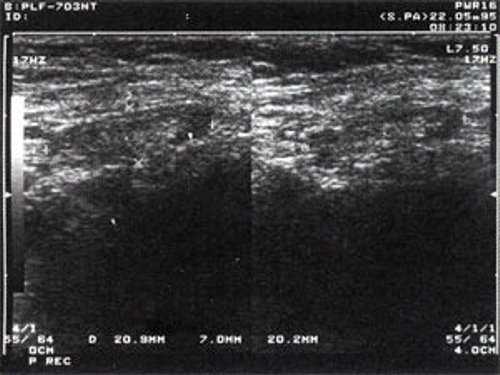

Практически во всех случаях дифференцировали лимфатический узел Кютнера (югулодигастральный), расположенный на границе средней и верхней трети шеи. Выявляемые лимфатические узлы имели размеры от 0,5 х 0,2 см до 2,3 х 0,8 см. УЗ-оценку производили после полипозиционного осмотра и нахождения самой длинной горизонтальной оси, что и принимали за максимальный поперечный диаметр. Большая часть лимфатических узлов (187) имели овальную форму с соотношением поперечного/переднезаднего более 1 (рис. 1 - 3). Тенденцию к округлению имели 30 лимфатических узлов, соотношение поперечного/переднезаднего приближалось к 1.

Рис. 2. Эхографическое изображение непальпируемого югулярного лимфатического узла на фоне остаточных явлений после перенесенного фарингита.

Рис. 3. Эхографическое изображение непальпируемого югулярного лимфатического узла без четкой клинической симптоматики воспалительного процесса в области головы и шеи.

Мы установили, что, как правило, более округлая конфигурация лимфатического узла при его размерах, превышавших 10 мм, сопровождалась небольшими болевыми ощущениями, и более выраженной простудной (воспалительного характера) симптоматикой. Лимфатические узлы менее 10 мм чаще всего плохо пальпировались, либо вообще не выявлялись пальпаторно. Во всех случаях эхографически хорошо дифференцировался гипоэхогенный кортикальный слой и широкое, средней или чуть ниже средней эхогенности изображение области ворот лимфатических узлов. Четкость дифференциации составных частей лимфатического узла была снижена при размерах менее 5 мм. Мы отмечали различную толщину гипоэхогенного изображения области коры лимфатического узла: от очень широкой - при выраженности или прогрессировании воспалительного процесса, до узкой - на фоне положительной динамики.